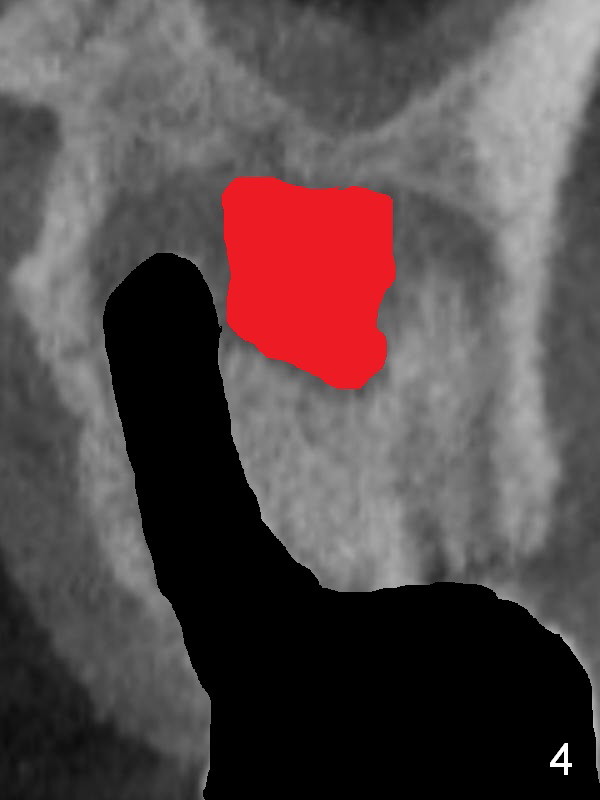

There is purulent discharge from the mesiobuccal fistula (Fig.1 <) during the tooth #14 extraction. Fig.2 is a coronal section of CBCT of the affected tooth showing a large apical lesion (*). When the tooth is removed (Fig.3), limited amount of granulation tissue is removed apical to the palatal root (P in Fig.2). The granulation tissue (Fig.4 red area) above the septum (Fig.3 S) is thoroughly extirpated when the septum is removed (Fig.5 black area).